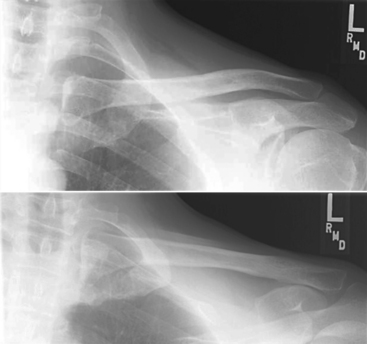

AP external and internal rotation (R)

AP external and internal rotation critique